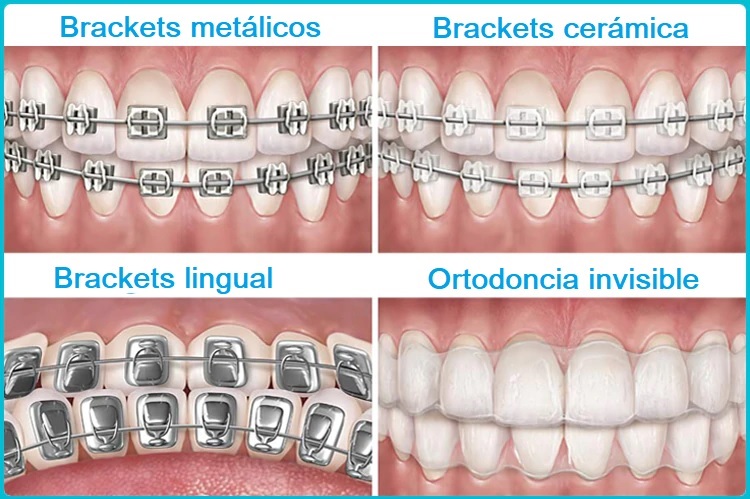

Tipos de ortodoncia invisible y diferencias

Tipos de ortodoncia invisible Existe una gran variedad de soluciones de ortodoncia invisible. Podrá elegir la opción que mejor se adapte a sus necesidades en función de la edad,...

Invisalign o brackets

Brackets y invisalign

Tipos de ortodoncia La ortodoncia es una especialidad de la odontología que se encarga de corregir la posición de los dientes. Restableciendo el equilibrio morfológico y...